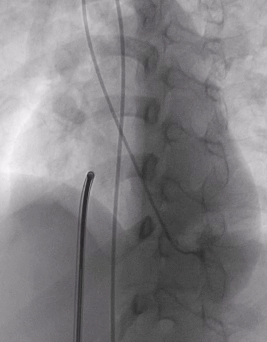

房间隔缺损介入封堵

根据术前测量结果,选择MemoSorb可降解ASD封堵器BDASD-I 14,配合14F可降解封堵器介入输送系统进行封堵。

建立输送轨道

导管导丝送入左上肺静脉

加硬导丝送入左上肺静脉,送入14F输送鞘

送入BDASD-I 14可降解ASD封堵器

展开左右盘面

左盘展开

右盘展开

锁定与牵拉试验

释放封堵器

释放后超声

超声下可见室水平和房水平都无残余分流